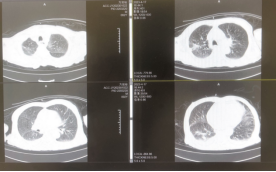

肺部CT:提示炎症存在